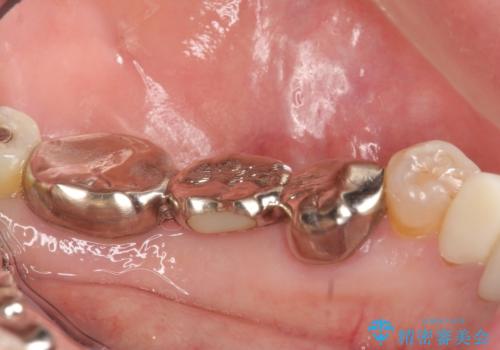

- 左下の銀歯を前の歯に合わせて白くしたいといらっしゃった方の症例です。

前歯部のシェードに合わせ、左下4及び左下567ブリッジをオールセラミッククラウンにて補綴しました。